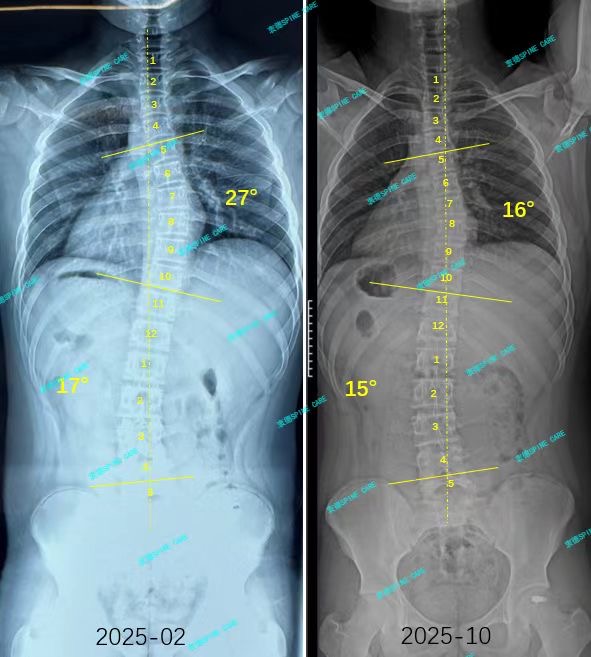

我是小博,从27到16度,我在衷德脊柱找回挺拔的自信!

案例主人:小博 发现侧弯年龄:14岁 侧弯情况:Cobb角测27°

在我的坚持戴支具和训练了半年后,脱支复查x片的结果显示我的27度侧弯减少到了16度!腰弯也下降了2度!更让我开心的是我的体态更挺拔了,高低肩也不明显了,穿校服时妈妈不再念叨“肩膀歪”。